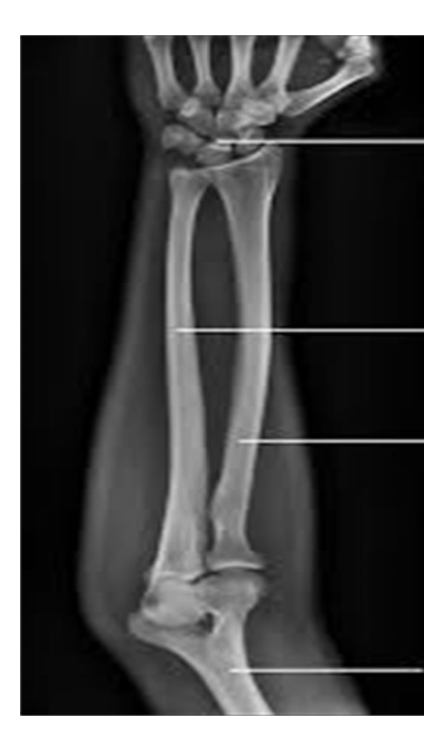

Identify the structures ? name of the bone ? View?

— Antero-Posterior

X-ray of forearm

Carpal bones

Ulna

Radius

Humerus